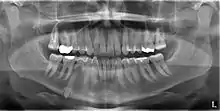

انطمار الأسنان الضرس المنطمر هو الضرس الذي لم يصل بروزه إلى القوس السني ضمن فترة النمو المخصصة لبروزه كاملاً، ولأن الضرس المنطمر لا يُكمل بروزه، فإنه يبقى على حاله طوال فترة حياة الشخص إلا إذا تم قلعه أو تم إجراء تدخل جراحي لإزالته، والضرس يصبح منطمراً نتيجة لوضع الأسنان المجاورة، مثل كثافة العظم المحيط، والأنسجة الفموية الزائدة، أو خلل وراثي وبأغلب الأحيان السبب في الانطمار يكون نتيجة لعدم وجود تناسب في الطول والمساحة الموجودة ضمن التقوس السني، التي تسمح ببروز الضرس، بحيث يكون الطول الكلي للتقوس العظمي أصغر نسبياً من التقوس السني (مجموع عرض كل سن من طرفيه الأنسي والوحشي). و بالنتيجة فإن الرحى الثالثة تكون منطمرة لإنها تعد من آخر الأضراس بروزاً في التجويف الفموي.[1] وتعد الرحى السفلية الثالثة هي الأكثر احتمالية للانطمار، وبعدها يأتي نظائرها من الرحى العلوية الثالثة، وكقاعدة أساسية، كل الأضراس المنطمرة يجب أن تقلع ما عدا الناب الذي قد لا يحتاج إلى تدخل جراحي ويبقى مدفون دون أن يسبب مشاكل مستقبلية .[2]

التصنيف يساعد الجرّاح بتحدبد مدى صعوبة إزالة الضرس المنطمر.[3] حيث يكون العامل الرئيسي المحدّد للصعوبة هو الوصولية أو إمكانية الوصول، بحيث تُحدد بالأضراس المجاورة أو أي شكل يعيق مسار الوصول. ومعظم برامج التصنيف ترتكز على تحليل صور الأشعة. و أهم العوامل ستناقش أدناه.

وهو أكثر التصنيفات شيوعاً فيما يتعلق بالتخطيط العلاجي. فبالاعتماد على الزاوية يمكن تصنيف الضرس إلى: